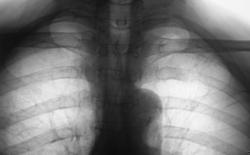

Левостороняя сегментарная очаговая пневмония.

Правостороняя очаговая пневмония в 6 сегменте.

Правостороняя очаговая пневмония.

Очаговая (сливная) пневмония в 6 сегменте.